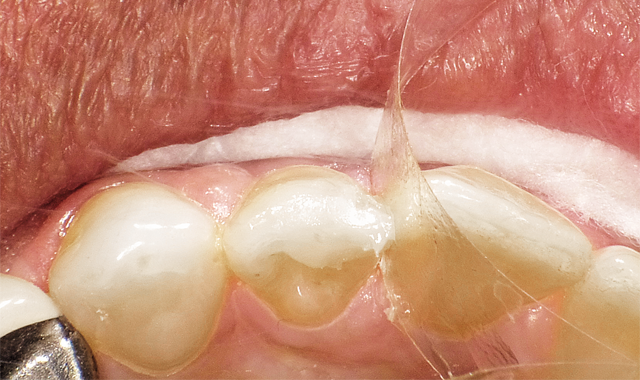

The challenge: Easy to onlay, easier to crown, far more of a challenge to place a direct restoration (Fig. 1).

In Case 1, it was a challenge to place a direct restoration.

After bevel placement, Palident Matrix System was put in place, followed by selective etching, rinsing, suction drying and application of a universal bonding agent (must be scrubbed for 20 seconds throughout the preparation due to selective etching), appropriate air drying and light curing (Fig. 2).

After bevel placement, Palident Matrix System in place, selective etching followed by rinsing, suction drying and application of a universal bonding agent appropriate air drying and light curing.